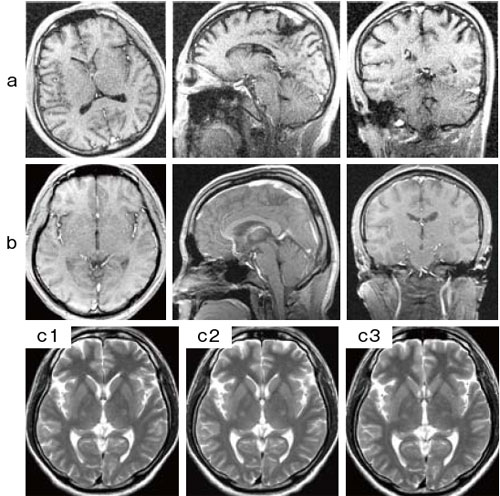

図3 Ready Brain

a,b:aに示すように頭部をわざと極端に傾けた状態でセットしても,Ready Brainの機能により基準線が自動的に設定され,bに示すような画像が得られる。(aはプランニング用画像)

c:同一被検者に対し,Ready Brainを用いて繰り返し撮像して再現性を検証したもの。c1は1週間前の画像,c2,3は同一日に頭部の位置を変えて撮像した画像,c3はaの頭部を極端に傾けて撮像した画像である。わずかな断面のズレはあるものの,良好な再現性が得られている。